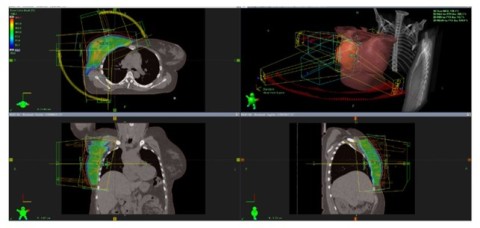

Oikean rinnan sädehoitosuunnitelma

Ennen sädehoitosuunnitelman tekemistä tietokonetomografiakuvista määritellään tarkasti hoitoalue sekä kriittisten elinten sijaintipaikat. Sädehoitosuunnitelmaa tehtäessä valitaan hoitokone, säteilylaji, energia sekä kenttien suunnat ja paikat hoitoa varten.

Suunnitelman avulla pyritään mahdollisimman tarkasti välttämään terve kudos ja suuntaamaan hoito syöpäkudosta sisältävälle alueelle. Myös kriittisten elinten suojaus määritellään suunnitelman tekovaiheessa.